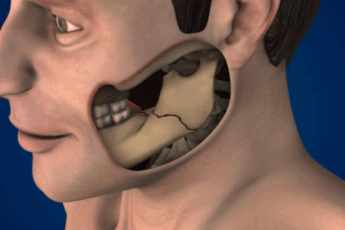

Absceso dental: una infección que causa dolor e inflamación alrededor de un diente.

Laceración dental: cortes o desgarros en los tejidos blandos de la boca.